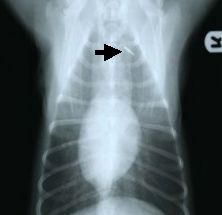

ISO規格のマイクロチップをISO規格用の「読み取り器」で読めばわかりますが、非ISO規格のものはISO規格専用の「読み取り器」では読めません。例えばマイクロチップをしてあるペンダンドのようなサインがあるのに「読み取り器」でよめない場合や、規格が違うため「読み取り器」で読めない場合に、マイクロチップ(MC)の有無を確認するには、マイクロチップ(MC)のありそうな場所を触診(手でさわりその感触で確かめる)で確かめることも猫の場合などは、可能な場合もありますが、最も確実なマイクロチップの存在する部位を調べるには、X線検査(レントゲン撮影)によってその有無を調べる方法です。

![]() |

マイクロチップを装着した犬のX線写真